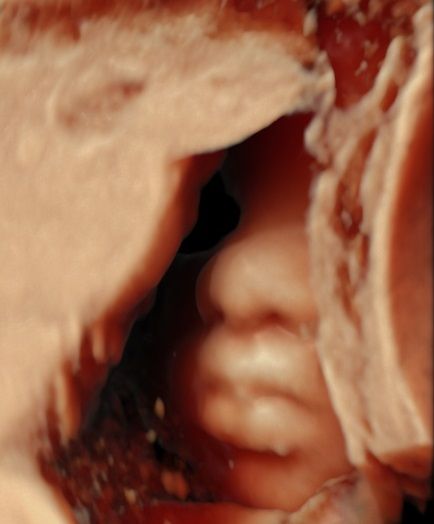

-certyfikat The Fetal Medicine Foundation (FMF) w zakresie badań prenatalnych w 11–13+6 tygodniu ciąży – przezierność karku u płodu (NT); kość nosowa u płodu (NB); przepływ w przewodzie żylnym u płodu (DV); przepływ na zastawce trójdzielnej (TR) oraz oceny ryzyka wystąpienia preeklampsji (stanu przedrzucawkowego) w ciąży.

Zdjęcia i filmy